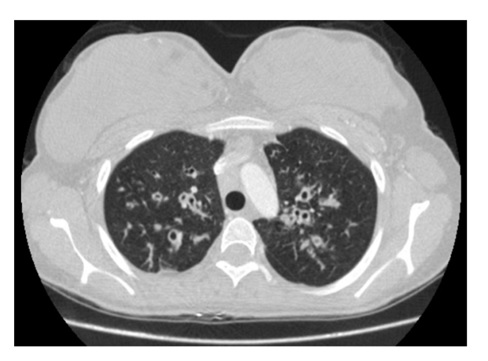

Chest X-ray showed increased streaking and train rail appearance in bilateral upper-middle zones (Picture 1). In the thorax computed tomography taken in an external center six months ago, there was centrally located bronchiectasis in the upper lobes of both lungs, accompanying peribronchial thickening and reticulonodular infiltrates (Picture 2).